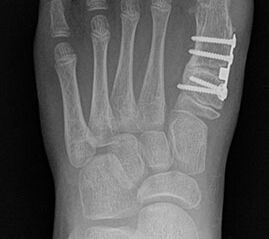

Standard ist die belastete Röntgenaufnahme des Fußes dorso-plantar und seitlich. Günstig ist eine Röhrenkippung von 10°-20°, um die Gelenke der Lisfranc-Linie einsehen zu können.

Bezüglich der Operationstechniken wird von früher häufig durchgeführten alleinigen Weich­teileingriffen am Großzehengrundgelenk aufgrund hoher Rezidivraten abgeraten 15. Die Operation nach Mc Bride mit lateralem Release, Exzision des lateralen Sesambeins, Abtragen der Pseudoexostose, Sehnenetransfer des M. adductor hallucis und mediale Kapselraffung zeigte unbefriedigende Mittel- und Langzeitergebnisse 16. Die Cerclage fibreux (mediale Kapselraffung) und das laterale Kapselrelease wird heute in Kombination mit einem knöchernen Eingriff angewendet. Bezüglich des Einsatzes von minimalinvasiven Operations­techniken vor Wachstumsabschluss liegen bisher keine Daten vor. Alle Osteotomien lassen sich nach Bedarf miteinander kombinieren. Es ist darauf zu achten, dass Osteotomien keine offenen Wachstumsfugen verletzen.

• Medial zuklappende Grundphalanxosteotomie nach Akin 17

• Subcapitale distale Chevron Osteotomie nach Austin 18

• Diaphysäre Osteotomie

• Scarf 19

• Ludloff 20

• Proximale Metatarsale I Osteotomien 21

• medial aufklappende Cuneiforme I Osteotomie 1522

• Nach Schluss der Wachstumsfugen: TMT I Arthrodese nach Lapidus 2425